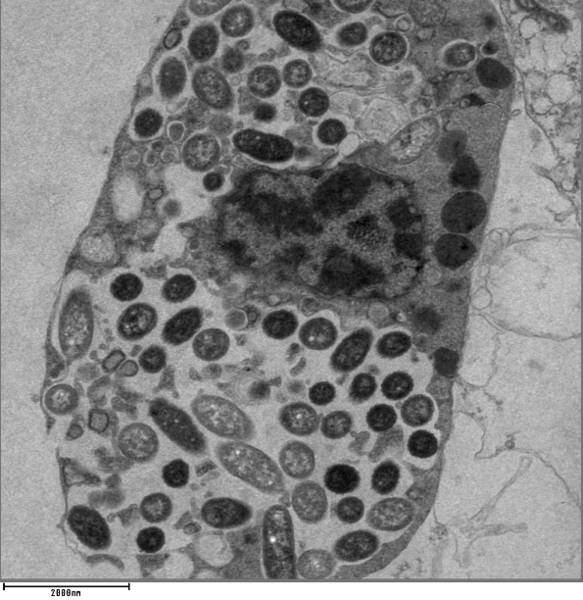

感染了嗜肺军团菌的细胞。图片来源:Clares back/wikipedia.org